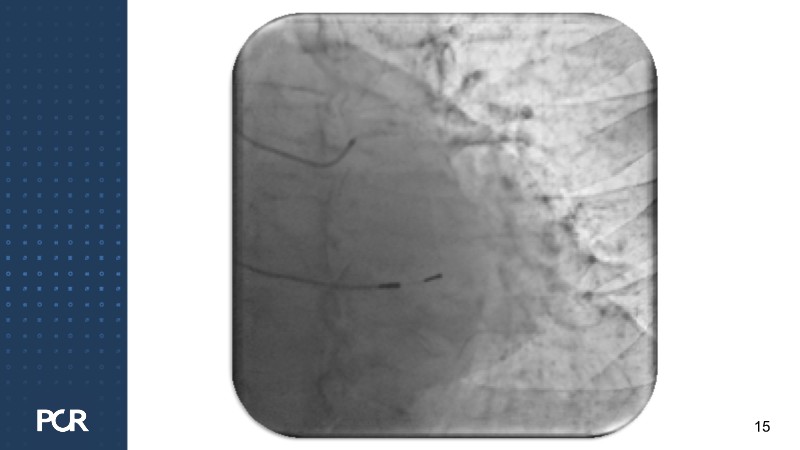

This session offers a comprehensive overview of the management of high bleeding risk (HBR) patients with multivessel disease. Through expert discussion and a live case demonstration featuring a complex elderly patient, it highlights how intracoronary imaging and physiology can guide procedural decisions and improve outcomes in this vulnerable population. The session also explores PCI strategies adapted to bleeding risk profiles, with a particular focus on the live case approach, including the use of sirolimus-eluting stents to optimise both procedural safety and long-term results.